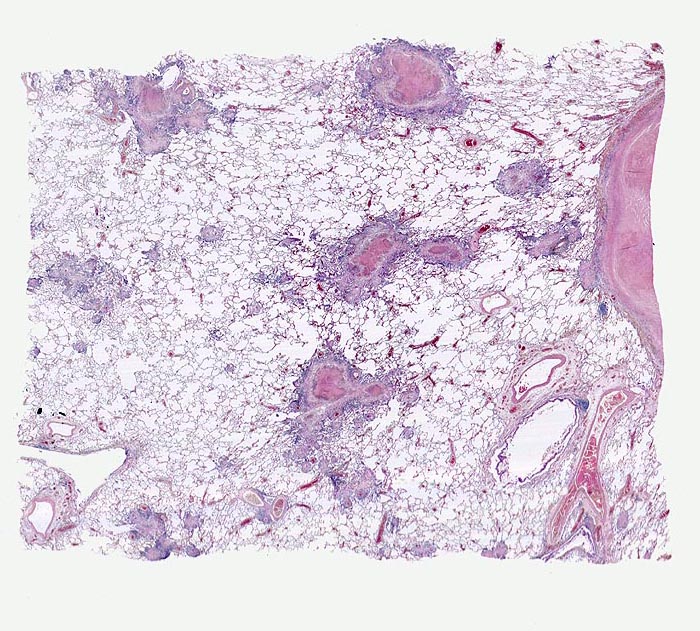

PathoPic – image database / PathoPic ID 4830 - azinös-nodöse Lungentuberkulose

azinös-nodöse Lungentuberkulose

Die Granulome sind jeweils in unmittelbarer Umgebung einer Arterie lokalisiert. Die tuberkulösen Herde gehen aus von vollständig oder partiell entzündlich zerstörten Bronchiolen (bronchogene Streuung). Die Granulome bestehen aus einer zentralen käsigen Nekrose umgeben von einem helleren Epitheloidzellwall und ganz aussen einem blauen Saum von Lymphozyten.

Autoptisch wird ein akuter Myokardinfarkt der Vorderwand diagnostiziert. In beiden Lungen fallen oberlappenbetonte knotige weisse, teils kleeblattartige Infiltrate auf und eine subapikal gelegene kleine Kaverne. Einzelne hiläre Lymphknoten der rechten Seite weisen Verkalkungen auf und bilden zusammen mit einem subpleural im Mittellappen gelegenen verkalkten Herd den abgeheilten Primärkomplex. In den käsigen Nekrosen können vereinzelte säurefeste Stäbchen nachgewiesen werden.

Die chronische produktive azinös-nodöse Tuberkulose entwickelt sich, wenn bei bronchogener Keimstreuung die Abwehrlage gut ist. Das käsige Exsudat imponiert makroskopisch als kleeblattartige oder knotige weisse Herde, die dem bronchoalveolären System entsprechen.